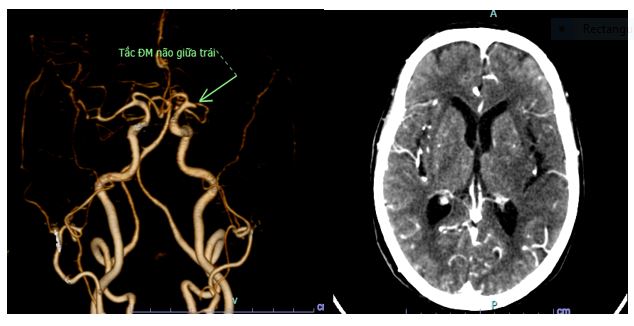

Bệnh viện Đa khoa tỉnh Phú Thọ vừa tiếp nhận và can thiệp thành công một trường hợp đột quỵ ở người cao tuổi, cụ bà 92 tuổi có tiền sử khỏe mạnh, chưa từng phát hiện tiền sử bệnh lý đặc biệt (tăng huyết áp, đái tháo đường,…) bị nhồi máu não cấp do tắc động mạch não giữa bên phải giờ thứ 6, đã rối loạn ý thức, khó nói, méo miệng, liệt 1/2 người phải.